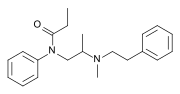

Ampromides

Structures

| Ampromides | ||||

|